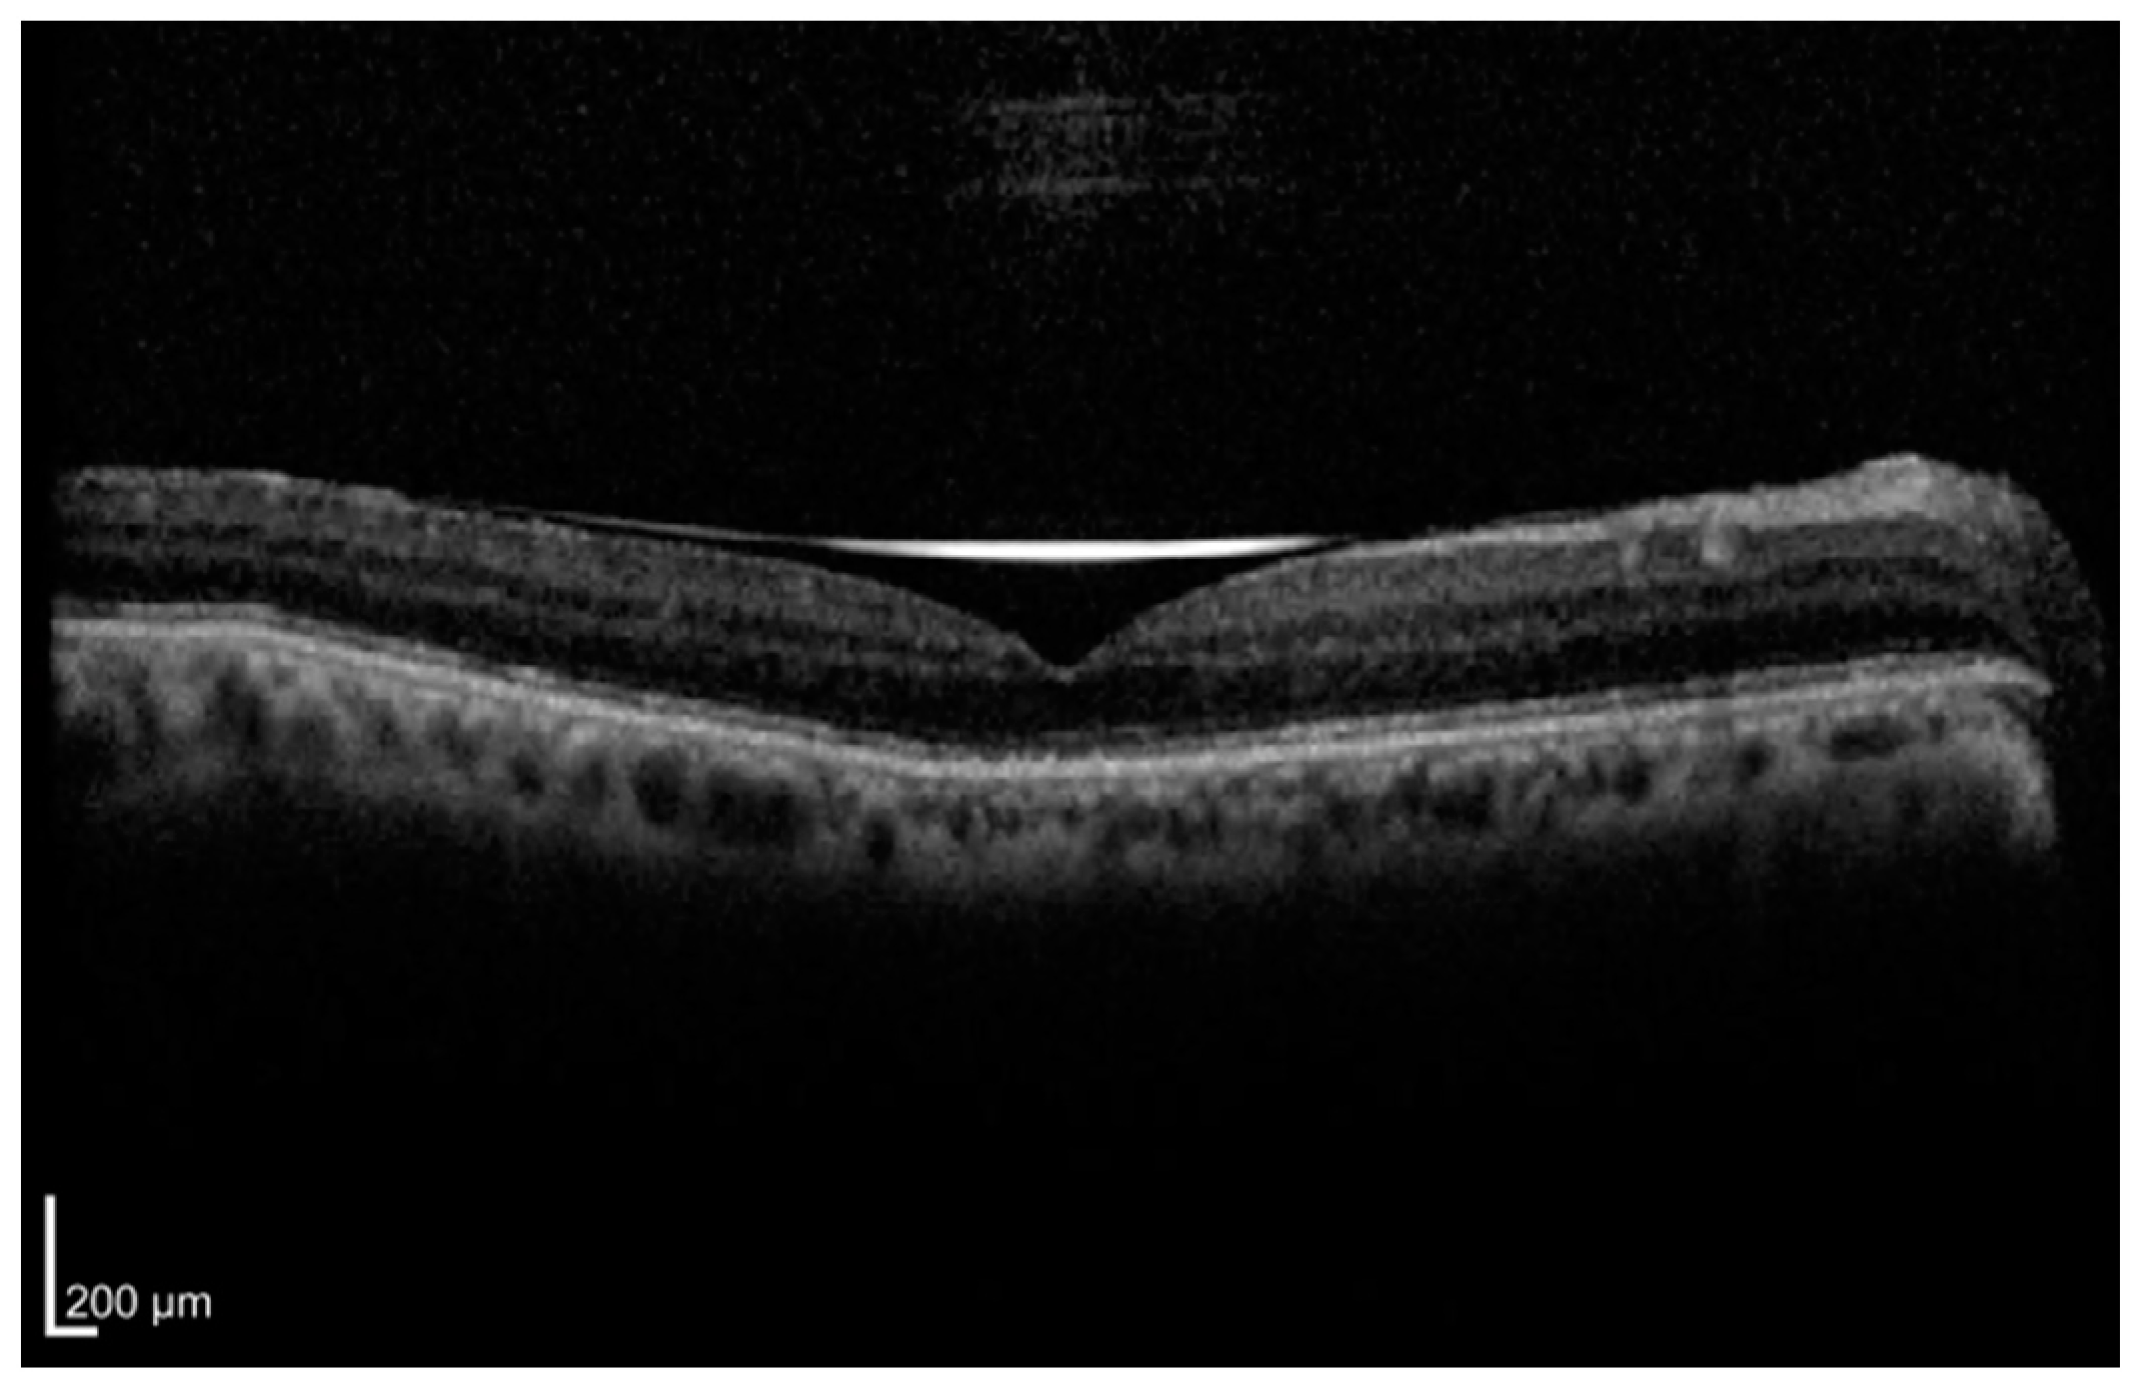

| Photoreceptor layer integrity (EZ and ELM) | Continuity of the ellipsoid zone (EZ) and external limiting membrane (ELM) indicate preserved photoreceptor structure | Intact layers have been shown to correlate with improved postoperative visual acuity, while disruption predicts poorer outcomes [10,11,12,13,14,15,16,17] |

| Height of retinal detachment (HRD) | Vertical distance between the detached foveal retina and the RPE at the fovea | Greater HRD is associated with worse visual outcomes, although some studies report mixed findings [23,24,25,26,27,28,29,30,31,33] |

| Retinal thickness parameters | Measurements of central macular thickness (CMT), outer nuclear layer (ONL) thickness, and photoreceptor segment length | While CMT and ONL findings are variable, longer photoreceptors segments have been linked to improved visual recovery [14,16,17,21,30,37] |

| Macular detachment | Involvement of macula in retinal detachment | Macula-off detachment results in worse postoperative outcomes when compared to macula-on cases [17,28,46,47,48] |